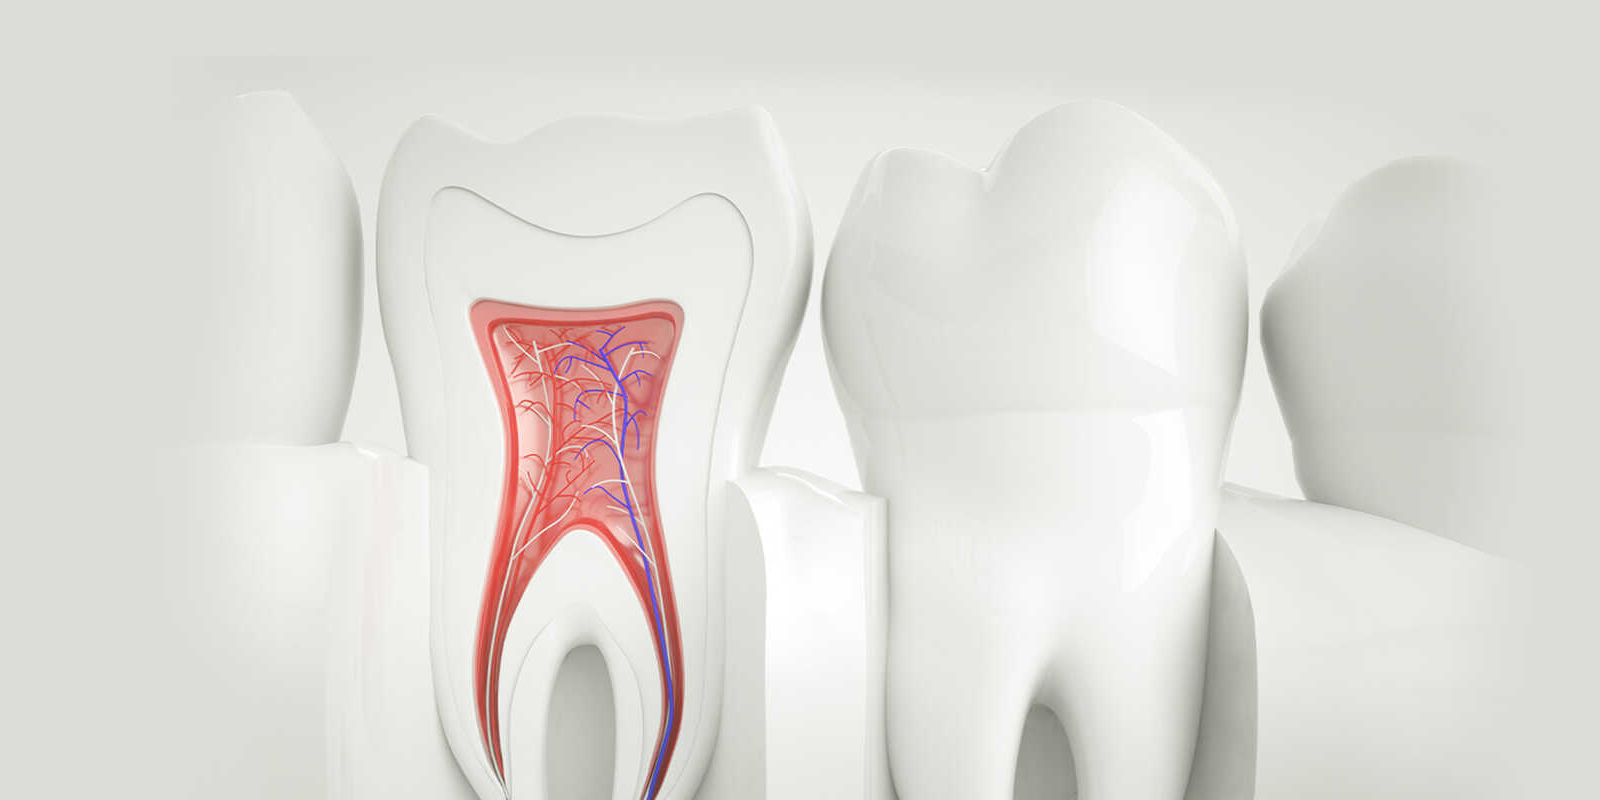

むし歯の進行・歯の破折・知覚過敏・かみ合わせ不良等により、歯の神経に刺激が加わっていると痛みがでます。冷たいものがキーンとしみたり、なにもしていなくても痛みがでることもあります。

2:歯の神経の先に膿がたまっているとき

むし歯の進行を放置したり、一度治療をした歯でも神経の穴の先で膿がたまると痛みがでます。膿は細菌の感染が原因です。ズキズキしたり、夜も眠れないほどの痛みになることもあります。

歯の根っこ(神経)の中から痛みや腫れの原因である「感染した汚染物」を、取り除く治療です。